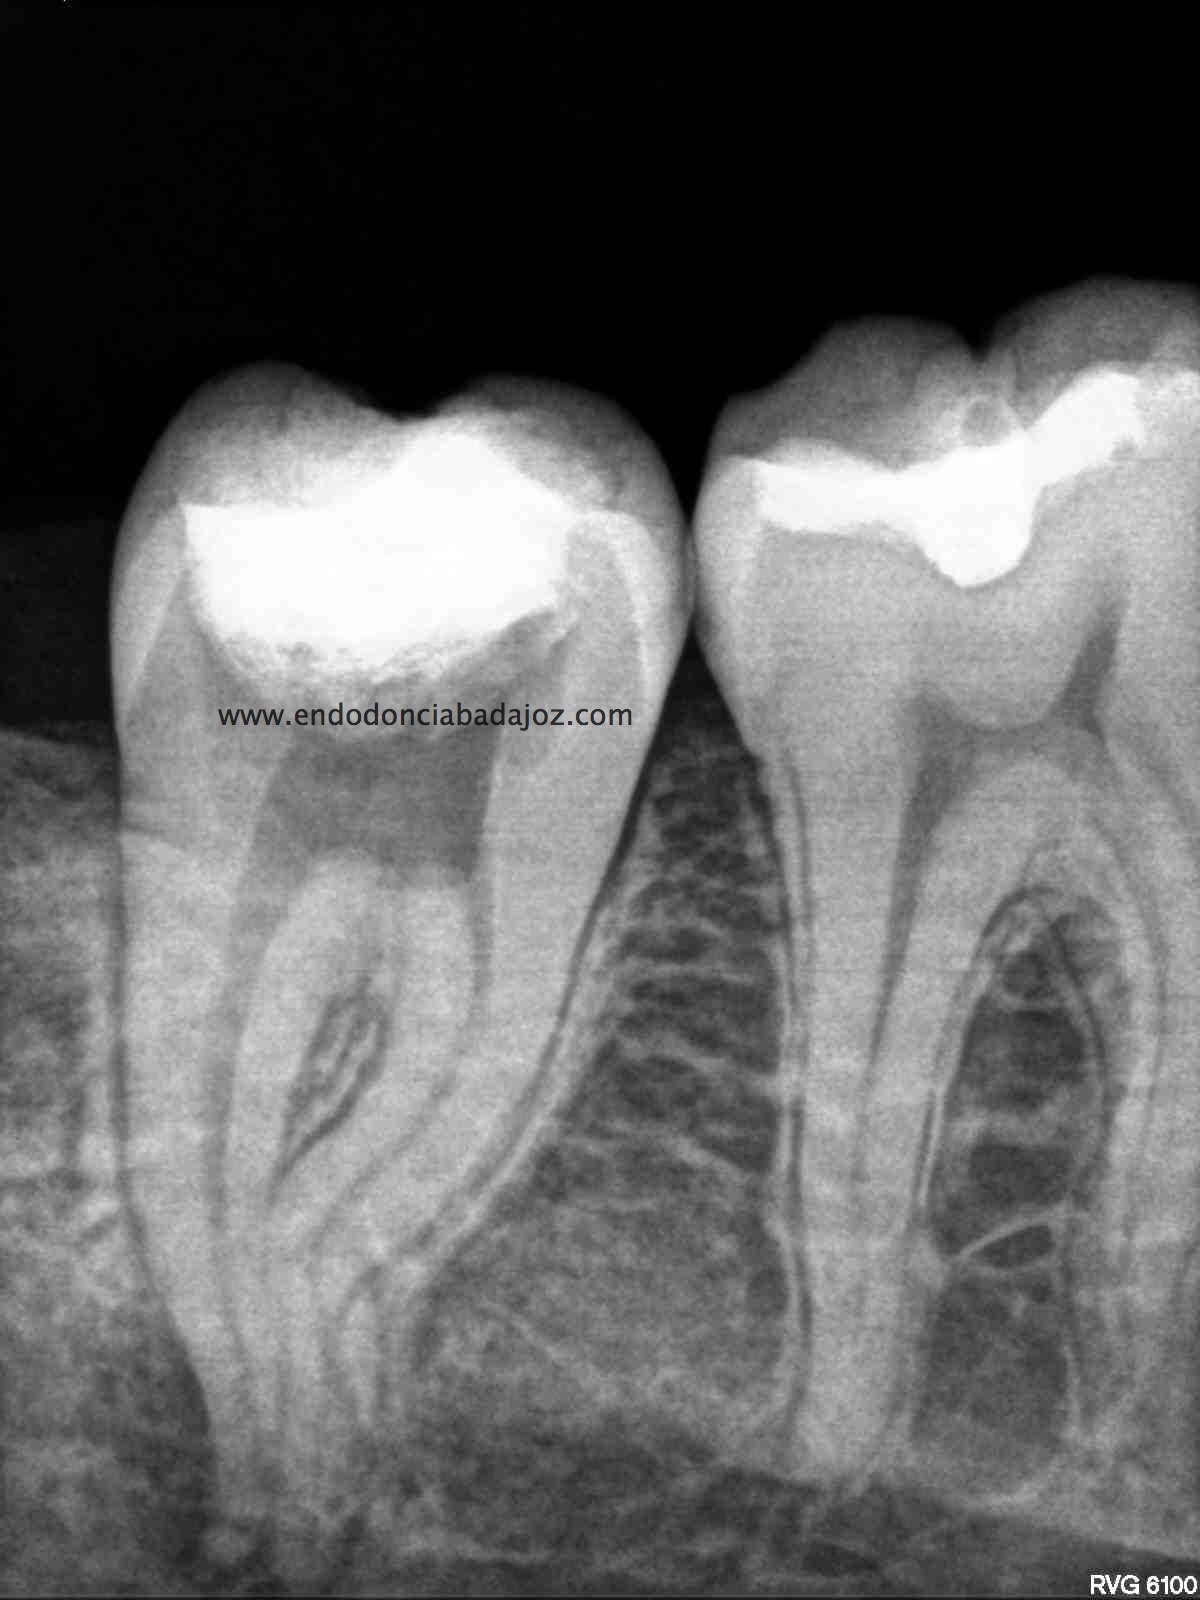

Sistemas de Conductos de un 4.7

Nos remiten a  la clínica una pieza 4.7, con necrosis pulpar y afectación periodontal, periodontitis apical:

La anatomía de los conductos nos hacia sospechar de un caso algo más complicado. Lo más complicado fue mantener la permeabilidad de los conductos. Instrumentamos con sistema rotatorio de Mtwo, mucha irrigación, se usó Irrisafe en los últimos lavajes, y como sistema de obturación usamos Condensación vertical con ola contínua, haciendo un backfilling con la Pistola Obtura II.

1. En los últimos lavajes??? hay Dr. Nieto cuántas influencias tiene usted.. Una vez más, hace que me enorgullezca tener un amigo así…eres un crack. cómo me gustaría saber que anatomía interna tiene este molar, y cuántas salidas tiene…hace donde irán esos conductos laterales presentes en los tres conductos? Qué difícil es manejar este caso, y lo importante que es no tener prisa por preparar el tercio apical en este tipo de curvaturas. Un abrazo…